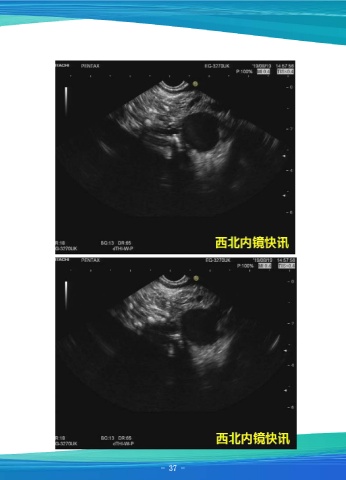

一例反复胰腺炎病例

资料提供:张排旗 西安市第三医院消化内科

患者男,40岁,近3年多次发作胰腺炎,未能明确胰腺炎诱因。本次再以“腹痛4天、

黄疸3天”于8月12日入院,行MRCP示胰头部胰管走行迂曲并呈串珠样改变,并远端轻

度扩张。于8月19日行超声内镜检查:扇扫超声胃镜扫查胰腺,胰头实质呈网格样高回

声,欠均匀,壶腹部胰管未见扩张,直径1.7mm,胰头部胰管壁粗糙,点状、条样高回

声,胰管下段可见一团块样高回声,截面大小4.3×2.5mm,远端胰管扩张,最宽处约

5.4mm,胰体部胰管扩张,胰腺实质回声尚均匀,胰尾部胰管、实质未见异常。胆管未

见扩张。镜下诊断:慢性胰腺炎,胰管钙化,胰管结石伴远端扩张。